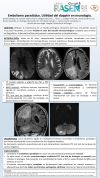

Angiopatía amiloide cerebral iatrogénica. A propósito de un caso